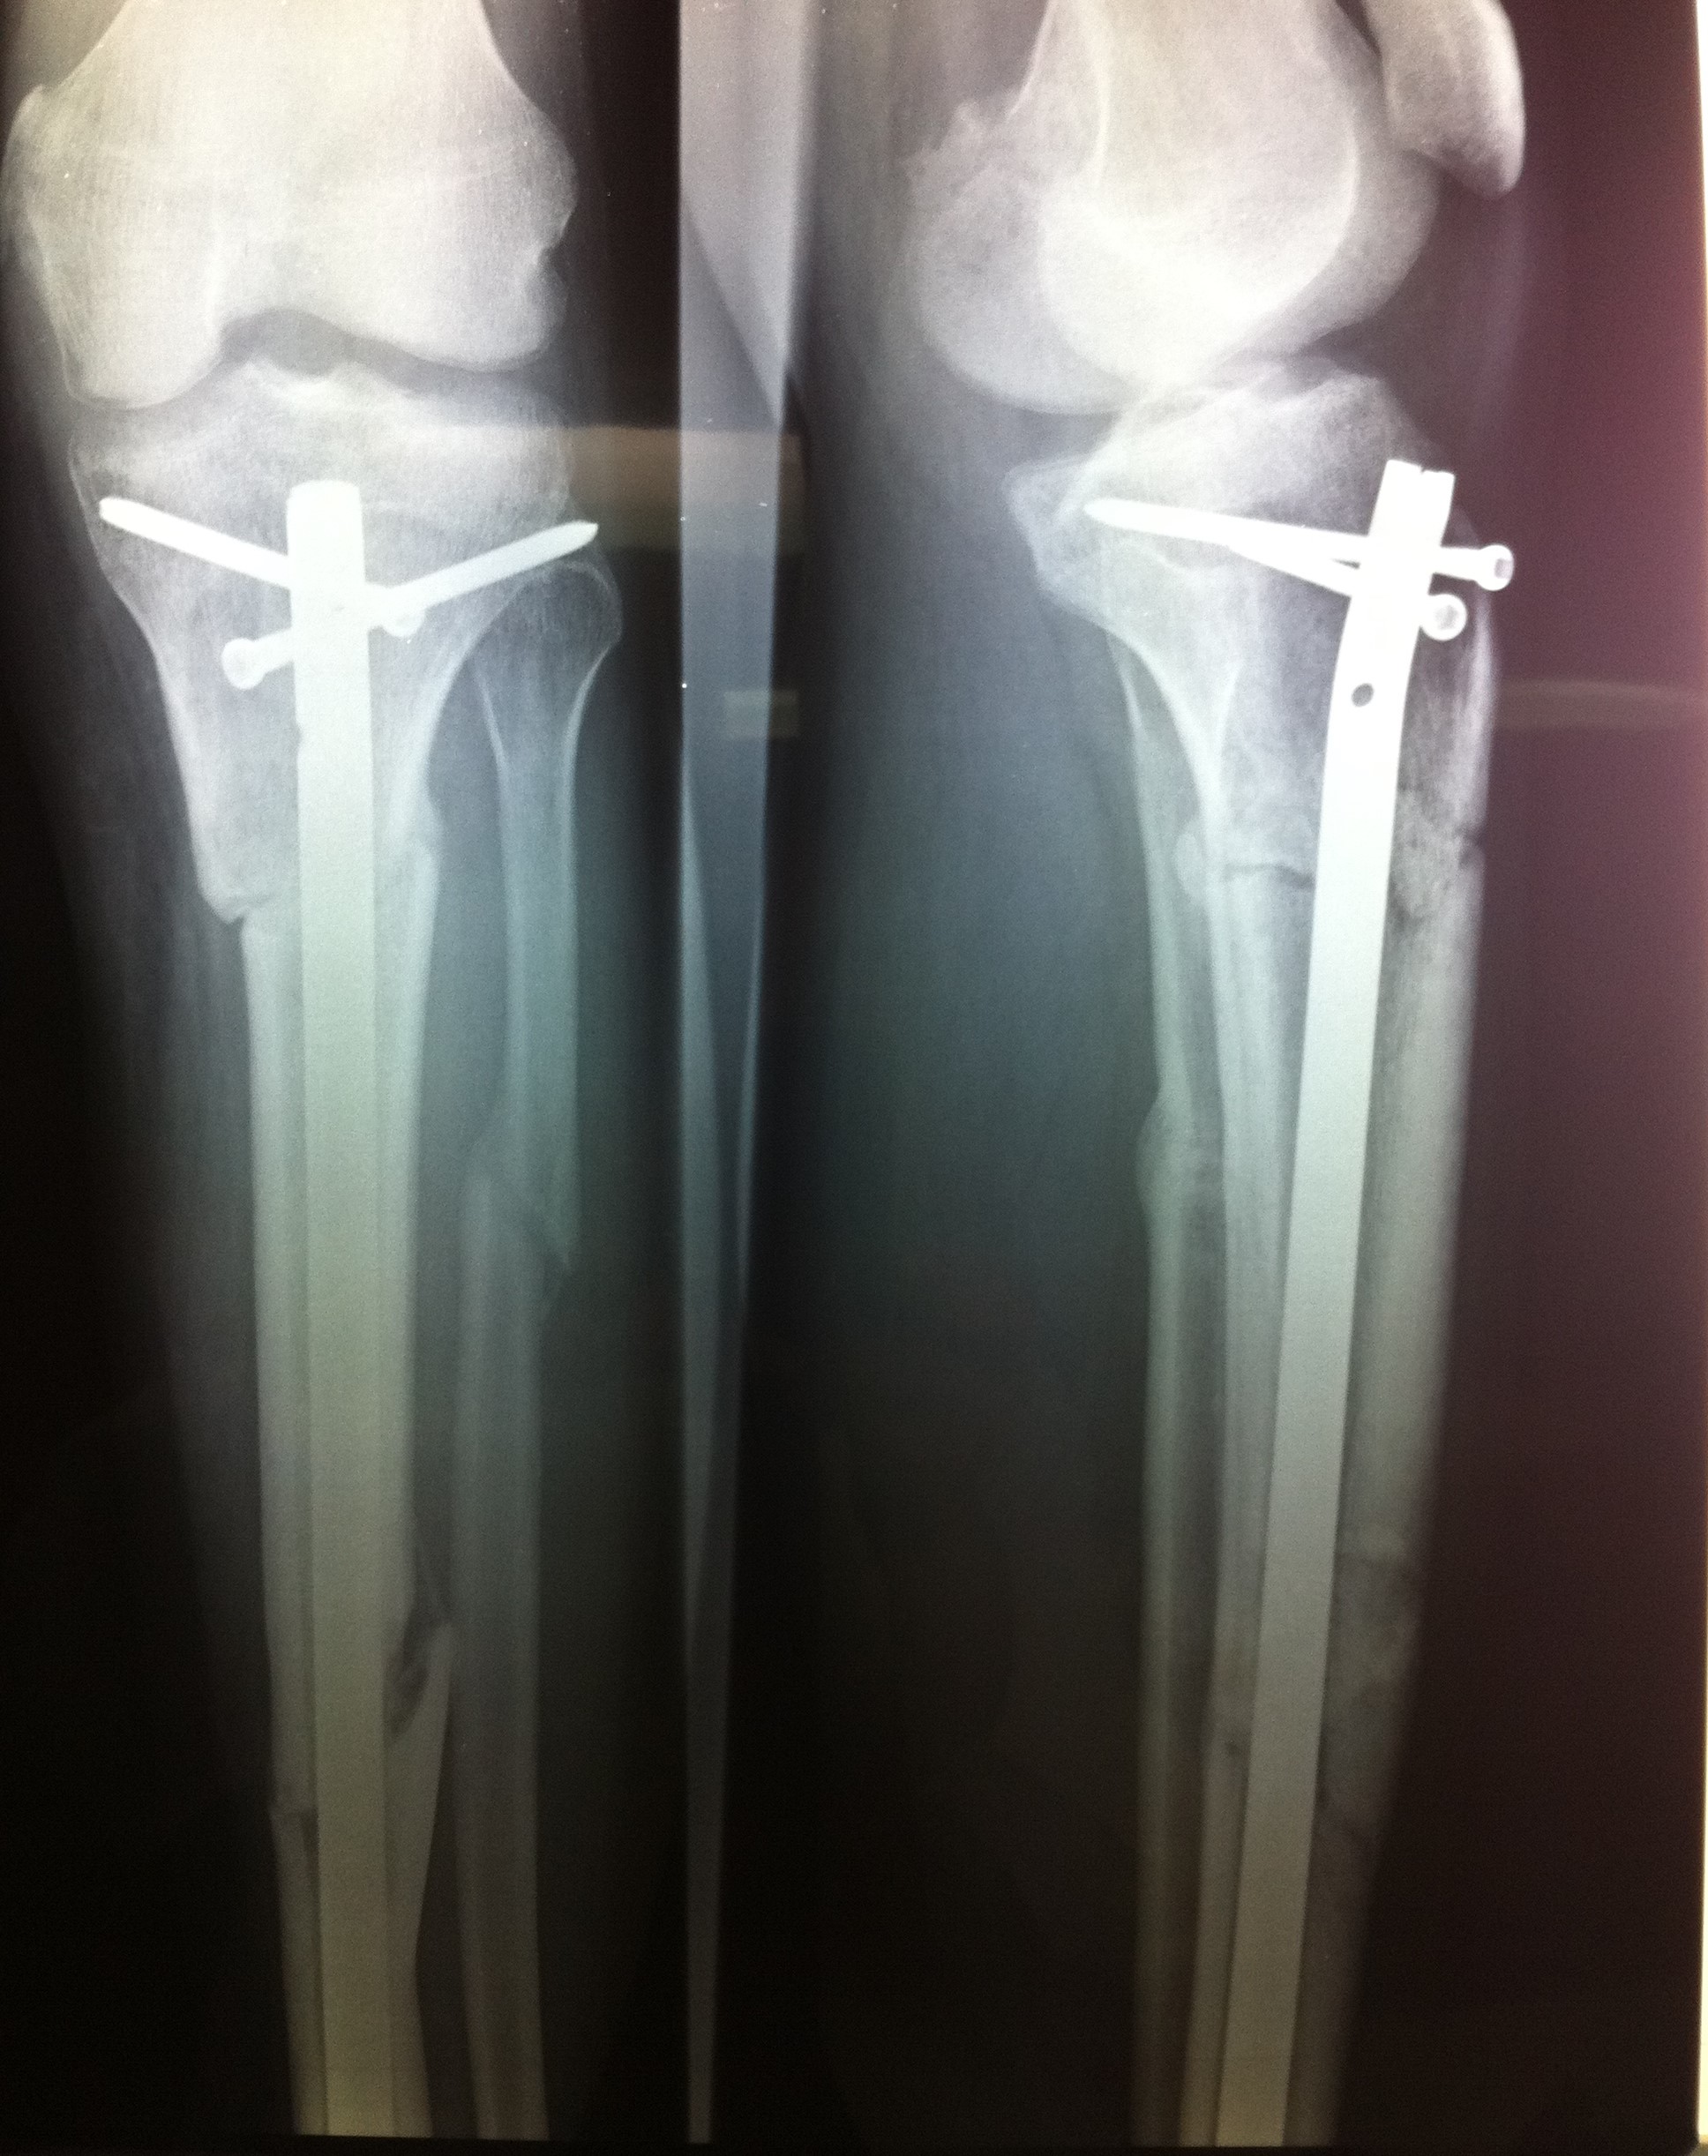

Από την άλλη, η χειρουργική μέθοδος που θα επιλεχθεί εξαρτάται από τον τύπο του κατάγματος, τις λοιπές συνοδές κακώσεις και την εμπειρία του χειρουργού. Ένα κάταγμα κνήμης μπορεί να αποκατασταθεί με τοποθέτηση ενδομυελικού ήλου, με ανοικτή ανάταξη και εσωτερική οστεοσύνθεση με πλάκες και βίδες ή με εξωτερική οστεοσύνθεση.